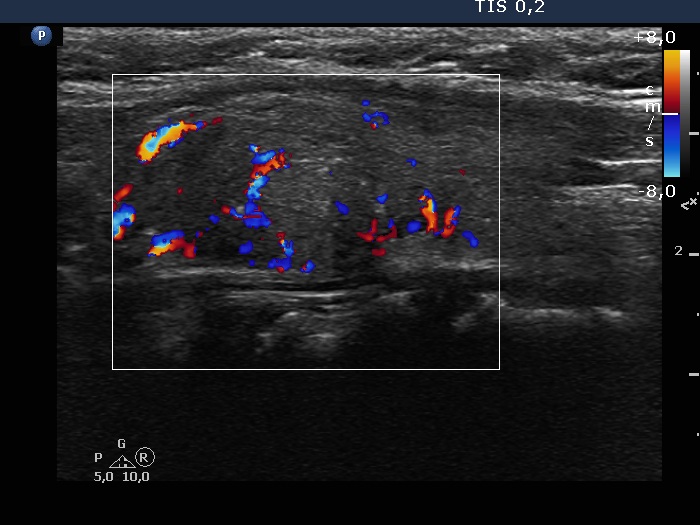

100 consecutive cases of papillary cancer - case 096 (ultrasonographic picture 8)

Left lobe, longitudinal scan, color Doppler mode. The lesion has both perinodular and intranodular vascularity.